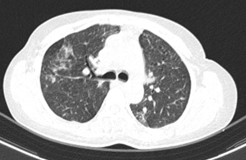

Hình 1: Hình ảnh tổn thương phổi trước điều trị: các đám tổn thương đông đặc, ranh giới không rõ, lan tỏa nhu mô phổi 2 bên.

Hình 9: Hình ảnh sau 6 tháng điều trị:  Các đám đông đặc và kính mờ 2 phổi (giảm số lượng và kích thước sau các đợt điều trị).